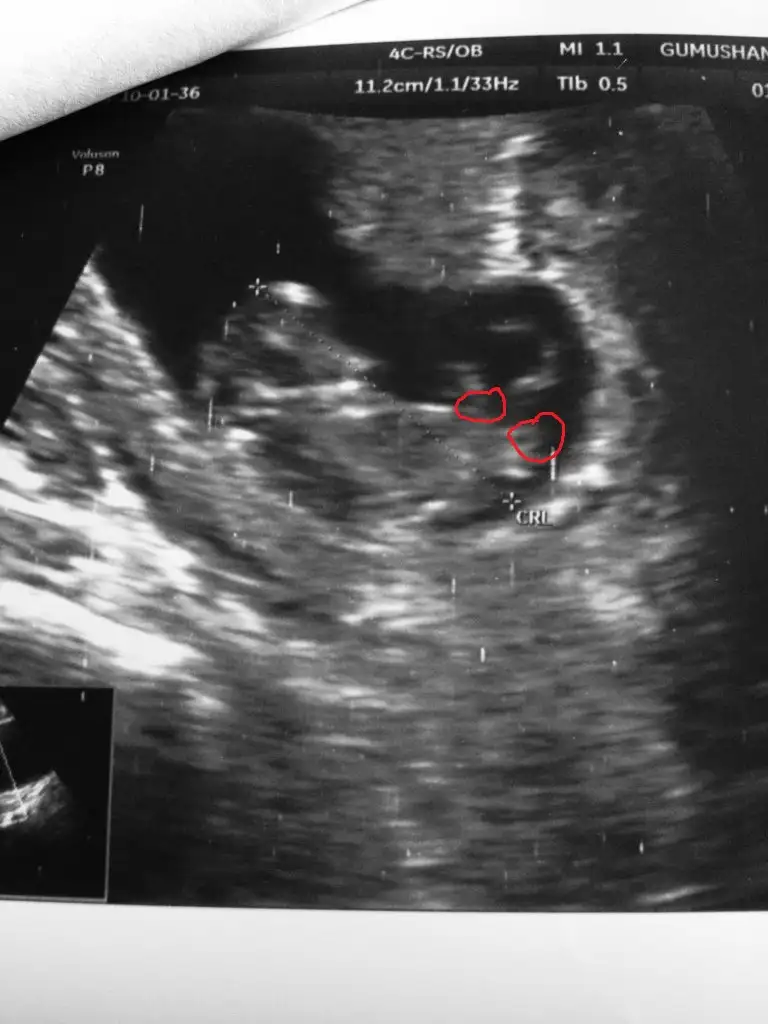

Ben anlamadim. Benimki Erkek mi kiz mi 13haftalikken erkek demişti doktor 15 haftalikken %90 kiz dedi yardımcı olur musunuz 7haftalik goruntusu